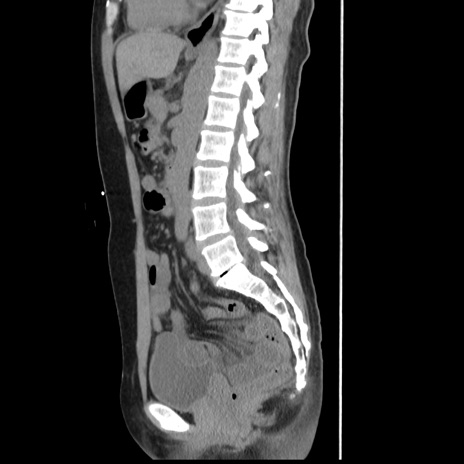

症例10(矢状断像)

【症例】 50歳代女性

【主訴】 腹痛

【現病歴】前日生レバーを食べた。今朝に排便あり。 昼前に突然発症の腹痛を生じ、当院救急外来を受診した。

【既往歴】 子宮筋腫にてで子宮全摘後

【身体所見】 意識清明、腹部:平坦、軟、下腹部やや左を中心に圧痛・反跳痛あり、筋性防御あり

【データ】WBC 7800、CRP 0.07